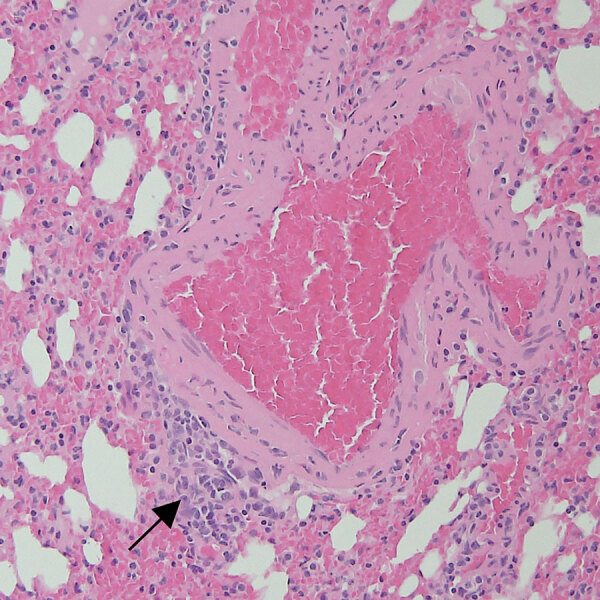

Description:We found similar mild perivascular inflammation in lungs of Bombali virus-positive and -negative Mops condylurus bats in Kenya, indicating the virus is well-tolerated. Our findings indicate M. condylurus bats may be a reservoir host for Bombali virus. Increased surveillance of these bats will be important to reduce potential virus spread.